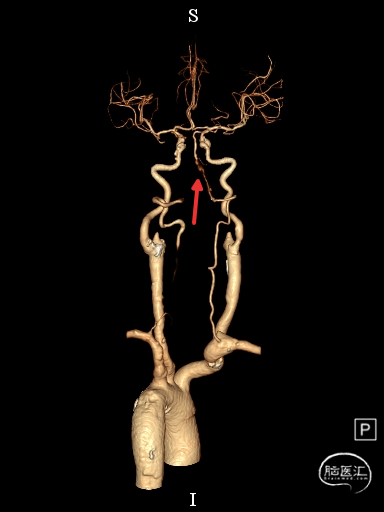

CTA提示:右侧椎动脉纤细,左侧椎动脉V1、V4段纤细。

术前DSA影像

右侧颈内动脉起始部中度狭窄,未见血流向后循环代偿。

左侧颈内动脉造影提示后交通开放,代偿供应后循环。

左侧椎动脉开口重度狭窄,前向血流缓慢,V4闭塞。